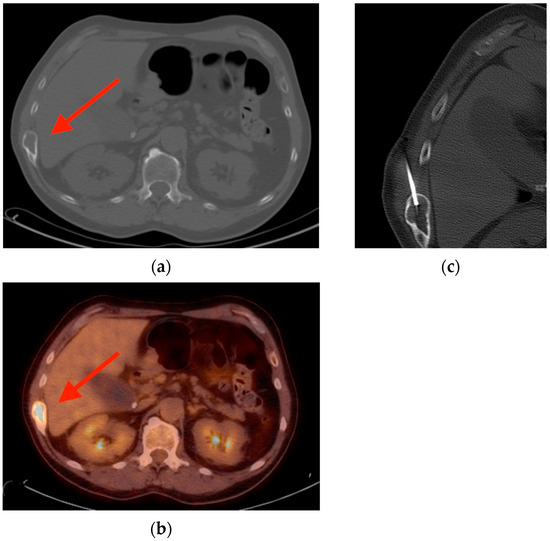

2.1. Fracture